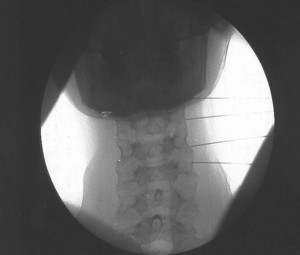

El paciente se coloca en decúbito supino con la cabeza en hiperextensión máxima y fijada a la mesa de quirófano.

Se posiciona el arco de fluoroscopia en visión lateral y se realiza una inclinación en el plano sagital (craneocaudales) para borrar el doble contorno de las vertebras. El punto diana es la intersección de las dos bisectrices del rombo formado por el pilar superior e  inferior del mismo nivel vertebral . Se marca el punto diana con marcador en la piel por detrás o posterior al musculo esternocleidomastoideo que coincida con el punto medio del macizo articular por donde discurre el ramo medial (centro del rombo). Se introduce la aguja bajo control radiológico, evitando la dirección anterior y medial para no lesionar la arteria vertebral, la raíz y el canal espinal. Cuando se obtiene contacto óseo, se posiciona el arco de fluoroscopia en posición AP y secomprueba comprobamos la posición de las agujas que deben situarse en la concavidad del macizo facetario o valle. La lesión de debe de realizar en el nivel afectado, el superior y el inferior realizandose al menos 3 niveles. Los segmentos inferiores de difícil visualización C6 y C7 se harán en decúbito prono y de forma similar a la denervación de las facetas lumbares. Se coloca inicialmente el el arco de fluoroscopia en AP, realizamos movimientos craneocaudales para quitar el doble contorno y posteriormente inclinamos el rayo en dirección oblicua ipsilateral unos 20º hacia la zona a tratar. Se dirige la aguja en visión túnel hacia el “ojo del perrito” para localizar el nervio mediante estimulación.